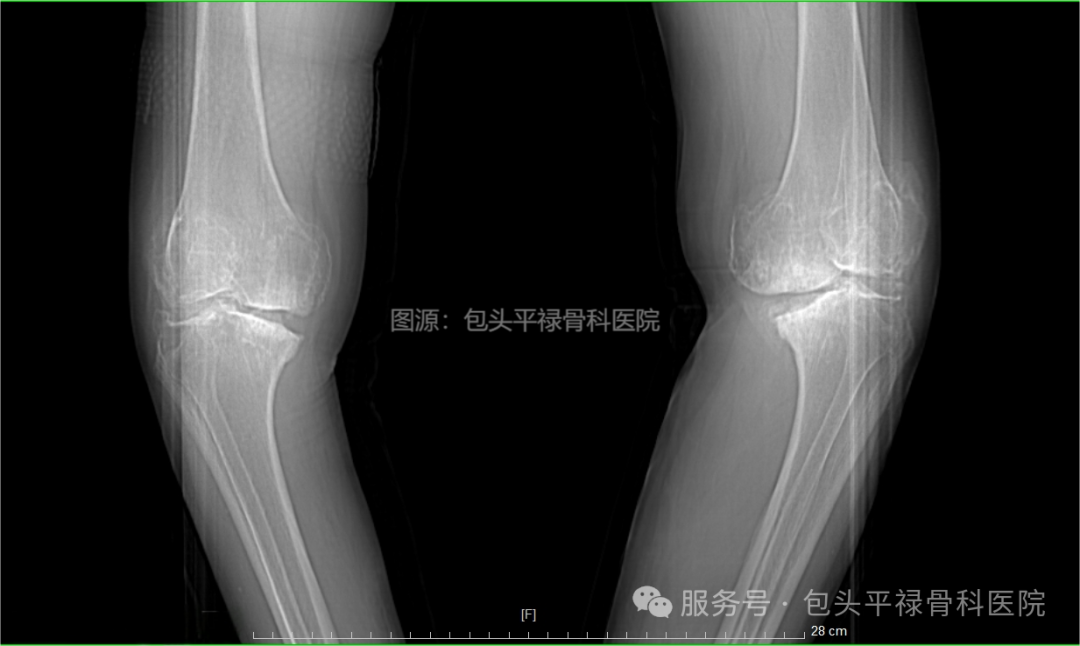

人工膝关节置换术前VS术后

提问 双腿均需进行膝关节置换时怎么办?

回答 建议年龄较大的患者,尤其伴有心脏病、高血压等,如双膝均需置换,先做一条腿,等2-3个月后,康复情况良好,身体状态佳,再做另一条腿。

年轻患者若身体状况良好,无糖尿病、高血压等问题,且关节畸形特别严重,遵医嘱可同时置换。